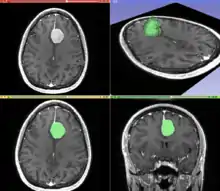

Image and sound processing

Information can take the form of images, sound, video or other multimedia. Bits of information can be streamed via signals. Its processing is the central notion of informatics, the European view on computing, which studies information processing algorithms independently of the type of information carrier – whether it is electrical, mechanical or biological. This field plays important role in information theory, telecommunications, information engineering and has applications in medical image computing and speech synthesis, among others. What is the lower bound on the complexity of fast Fourier transform algorithms? is one of unsolved problems in theoretical computer science.

| FFT algorithms | Image processing | Speech recognition | Data compression | Medical image computing | Speech synthesis |